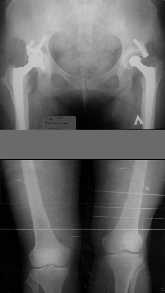

Прежде всего необходимо выполнить рентгенографию в таком положении, как это показано на рис.

После этого представится возможность оценить ось и сравнитьеё с нормой Рисунки из кники Dror Paley - Принципы коррекции деформаций. Этой теме посвящены 800 страниц. Хотя, учитывая контрактуру, это исследование не будет исчерпывающим.

1. Иллюстрации - во вложении.

Два бедра после эндопротезирования.

Авторы операции долго думали почему больная хромает.

Сдклали снимок - одна нога короче почти на 3 см.

Здоровый человек и то будет хромать.

2. Другой пример - дефект после инфицирования коленного эндопротеза.

Предполагалось, что величина дефекта 11-12 см. Так получается, если

сделать снимок только области коленных суставов. Определить

укорочение сложно, так как нога просто болтатется.

Сделали снимок "от и до" - величина дефекта 17 см.

Правда эта иллюстарция сделана на цифровом рентгеновском аппарате.

Больной стоит, а трубка передвигается сверху вних, последовательно

выполняя рентгенограммы. В данном случае - 4 штуки.